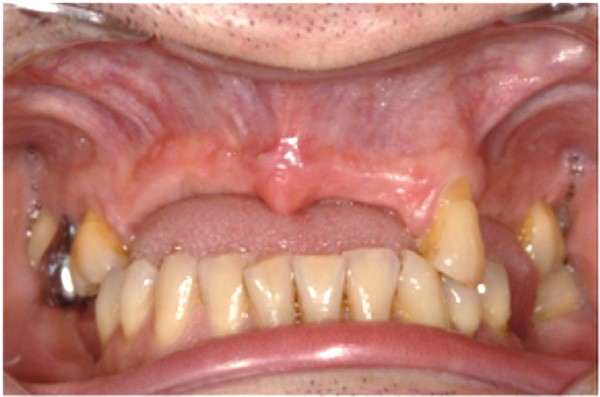

Le deuxième volet de la conférence traitait des ostéotomies segmentaires au cours desquelles un segment d’os alvéolaire (avec ou sans les dents) est déplacé. Cette technique chirurgicale consistant à libérer un segment plus ou moins étendu du prémaxillaire assure la reconstitution du capital squelettique dans le sens vertical et sagittal respectivement à l’aide des greffes simultanées d’interposition et d’apposition.

Cette partie de la présentation ne se contentait pas de rapporter les principes précédemment décrits à des régions limitées des maxillaires mais étendait la discussion à la difficulté majeure rencontrée en implantologie : rattraper des erreurs de positionnement implantaire ayant entraîné des compromis prothétiques inesthétiques. La solution thérapeutique mise en œuvre par Benoît Philippe consiste à appliquer la procédure d’ostéotomie segmentaire à l’entité constituée par l’os alvéolaire péri-implantaire et les implants. Les couronnes implantaires sont déposées. Le tracé d’ostéotomie encadre le segment à repositionner mais n’implique pas la corticale palatine qui sera fracturée pour éviter toute lésion du périoste (nourricier du segment alvéolo-implantaire). Un dispositif prothétique préparé en amont guide la translation du fragment qui est fixé au moyen de plaque d’ostéosynthèse dans la situation idéale. Le capital squelettique est reconstruit et l’espace prothétique disponible est normalisé.